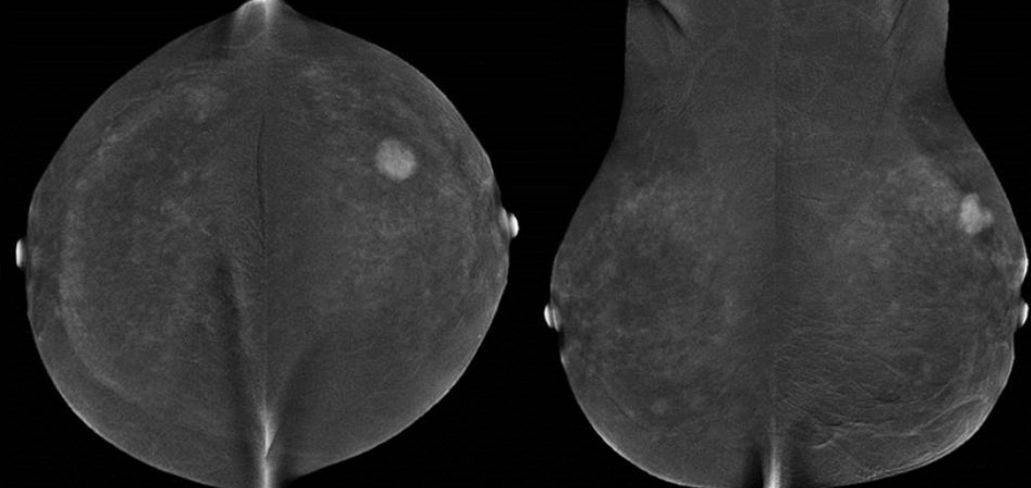

Kontrastmittel-Mammographie: Low-Energy-Bild

Kontrastmittel-Mammographie: Rekombinationsbild